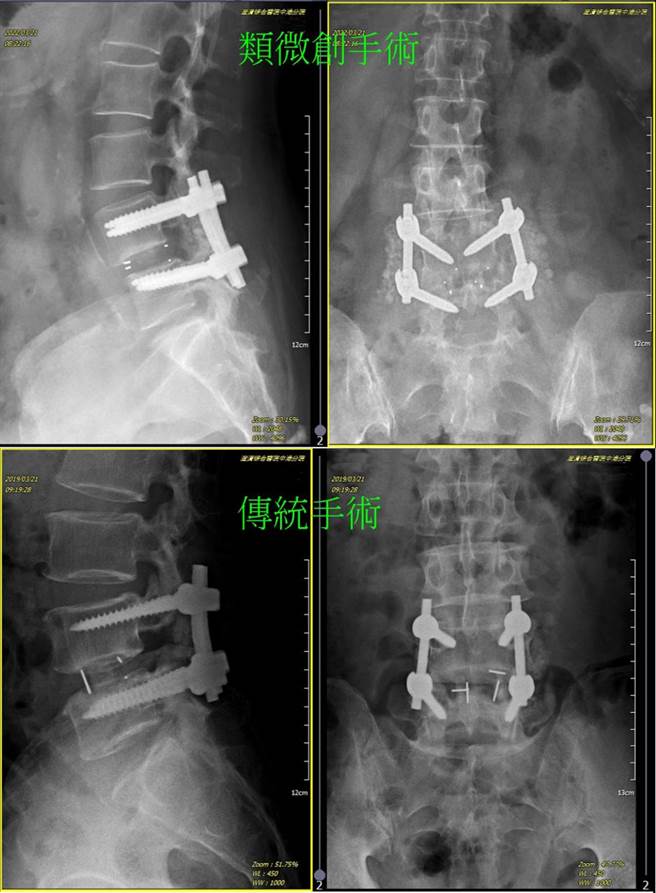

澄清医院骨科医师钟文隆表示,类微创脊椎手术手术传统切口进入后,不会剥离脊椎旁的肌肉,而採用背肌外侧沿肌纤维走向,可以深达腰椎患部需钢钉植入的椎节地方,再进行钢钉植入。(澄清医院提供/冯惠宜台中传真)

钟文隆解释,所谓的「类微创脊椎手术」,关键在手术入刀的位置,是以传统切口进入后,不会剥离脊椎旁的肌肉,而採用背肌外侧沿肌纤维走向,可以深达腰椎患部需钢钉植入的椎节地方,不破坏且仅拨开肌纤维,进入患部先进行清除压迫神经外围的组织,再进行钢钉植入,就大功告成,完成脊椎手术,其手术时间仅微创手术的一半。